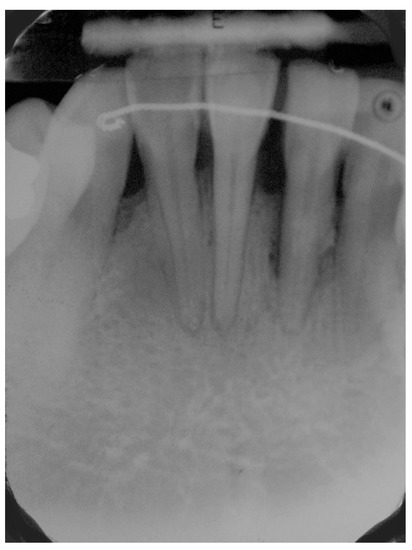

5. Materials and Methods

6. Results